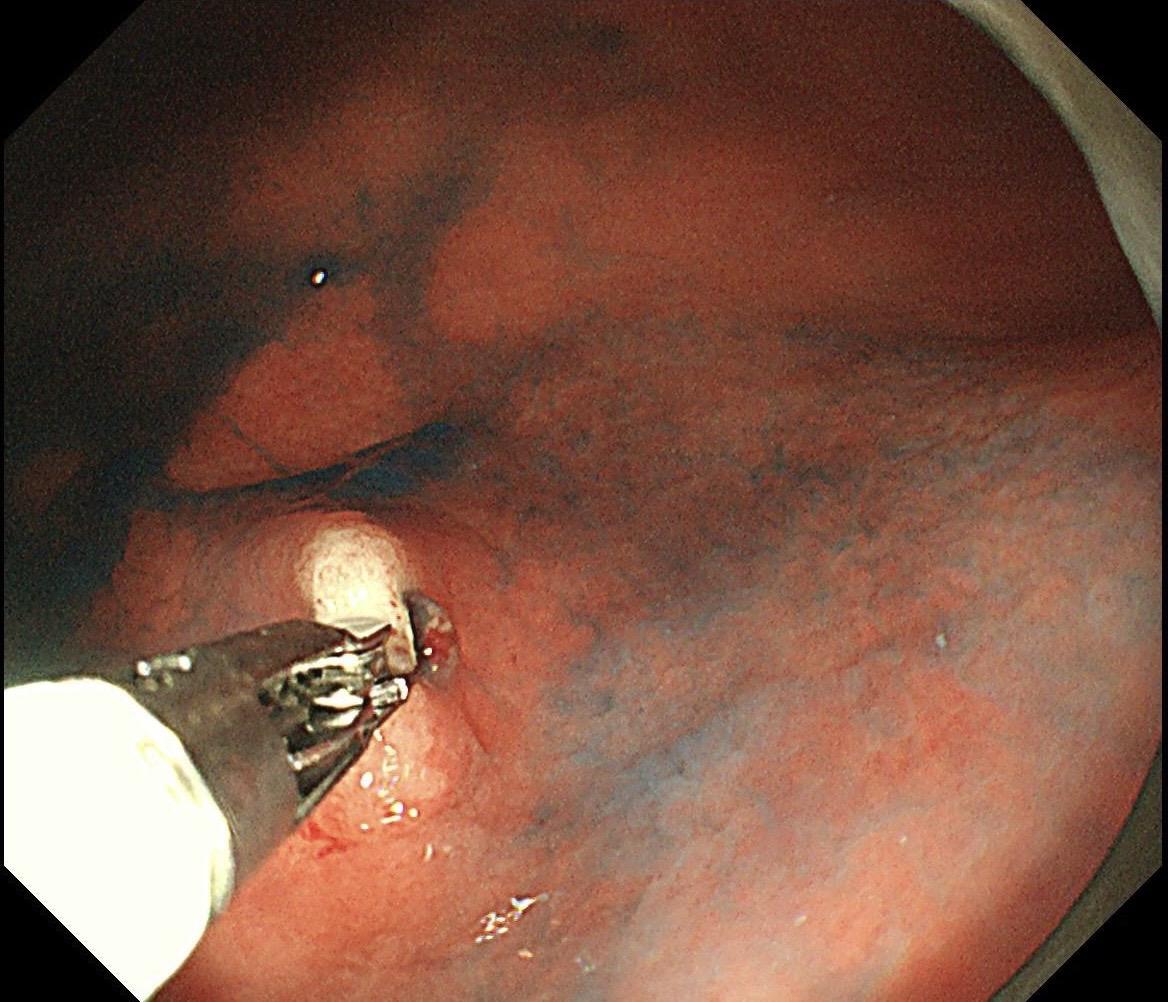

男,40岁,胃双发褪色调病变。慢性胃炎复查,3年前胃镜未见异常,Hp阳性背景,萎缩不明显,胃体下部大弯见一褪色调病变,浅凹陷,5mm左右,换用放大内镜观察,表面结构缺失,血管异型明显,未分化可能性大……胃窦后壁见一白斑,无高度差,NBI浅茶色,放大草草看了下,似有边界,IP增宽,活检待病理……小哥哥胖得几乎没脖子,腹式呼吸太明显~😖